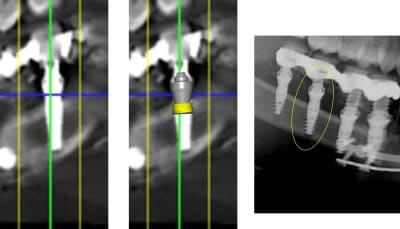

a parce qu il faut etre expert pour voir que les deux derniers implants sont clairement pas dans l os ??

1 se baser sur la pano pour en tirer des conclusions est une erreur de débutant

2 sur les coupes scanner une partie du col est infra osseuse et l'autre non

> 1 se baser sur la pano pour en tirer des conclusions est une erreur de débutant

>

> 2 sur les coupes scanner une partie du col est infra osseuse et l'autre non

mais posit... y'a que toi qui pense que l'implant est aussi enfoui... ca saute aux yeux que tu fais tout pour grater 1mm d'enfouissement... pour qu'ils paraissent pas si mal posé que ca...

avec, par exemple, ton implant de 10mm qui est contenu dans 9mm... t'es le Gérard Majax des guides chir.

comme ici... si e carré fait 4,5 alors l’implant ne fait pas 10 mais moins de 9...

Tout comme l’autre implant pas 11,5 mais 10,3

heureusement que ta méthode est "précise" ;)

mais si tu t'intéressais un peu à la littérature tu saurais que ce n'est pas un problème dans ce cas clinique et tu ne serais pas obligé de mentir en dessinant n'importe quoi

En traçant le col de l'implant comme tu le fais tu ne tiens pas compte que le pilier fait 4,5 mm de hauteur, normalement tu devrais arriver à le comprendre tout seul !

Pour le reste de la discussion que le col ne soit tout infra osseux oui mais pas "5 spires" et tout les implants sont en bi corticale. Lorsque tu dis à quelqu'un qu'il est de mauvaise foi vérifie en premier tes arguments. Pour le col dans un cas comme celui là ce n'est pas un problème.